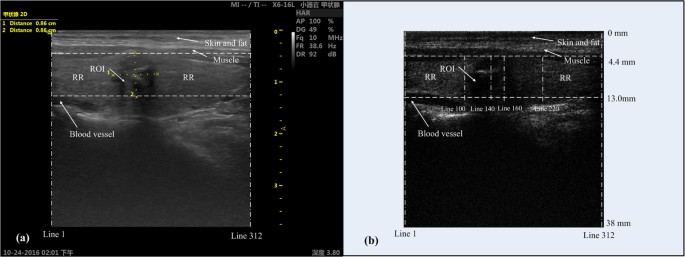

This method was performed by assuming that the amplitude of the echo signals along the scanning lines in ROI were distributed differently with those in reference region (RR) which has no pathological change. Figure 3 illustrates a typical thyroid nodule in both the B-mode image (a) and corresponding RF image frame (b). In general, the RF image frame (e.g., Fig. 3b) was constructed through the following processes: 1) acquiring raw RF data using the diagnostic ultrasound system; 2) extracting 2nd harmonics from raw RF data by applying a band-pass filter (7.5 MHz~12.5 MHz); 3) deriving the envolpes of filtered 2nd harmonic signals by Hilbert transform; and 4) transferring 2nd harmonic amplitudes to gray scale values and constructing the gray-scale RF image.

To show the distribution difference between the two regions, four different scanning lines in one frame of RF data of sample No. 2 were selected, viz., 140th line and 160th line in ROI, 100th line in the left RR, and 220th line in the right RR. The regions and lines are illustrated in the image of the RF frame (Fig. 3b). The total scanning depth of the RF frame shown in Fig. 3b is 38 mm, and the depth of selected region is between 4.4 mm to 13 mm. The nodule position in the RF frame (Fig. 3b) might be slightly different with that in the B-mode image (Fig. 3a) due to slight movement of the sonographer or the patient. Figure 4 illustrates the RMS amplitudes calculated for the 2nd harmonic signals along individual lines in selected regions (viz., Lines 100, 140, 160 and 220). The RMS along two lines in ROI is generally lower than those in RR, indicating obvious hypoechogenicity structure of malignant nodules. Then, the empirical cumulative distribution functions (CDF) of the RMSs along individual lines were calculated to illustrate the distribution difference between ROI and RR as shown in Fig. 5. If the two groups distributed similarly, their CDFs should be close. However, one can observe in Fig. 5 that, the CDFs of the lines in RR are near to each other, while far away from the CDFs of the lines in ROI.

As shown in Fig. 3a, there are always some other tissues (e.g., blood vessel, muscle, skin and fat) surrounding the ROI, which might be irrelevant to the diagnosis of nodulus. Therefore, in order to save the computation time, a band between two horizontal dash lines in Fig. 3b is selected as the processing area following the principle that the upper and lower boundaries of ROI are completed covered. The ROI was defined by experienced sonographer in this study. The rest part in the selected area other than ROI was regarded as normal tissues without pathological changes and could be used as the reference region for ROI (viz., RR). Then, a group of RMSs of the 2nd harmonic signals was calculated for individual lines in the processing area. To quantify the abnormality of the thyroid nodule, the RMSs of each line in the 2nd harmonic RF image were compared with the RMSs obtained for individual lines in RR one by one, through two-tailed two sample K-S test. The two-tailed two-sample K-S test quantifies a distance between the empirical distribution functions of two samples, and returns asymptotic P-value which presents the similarity of the two distributions. The P-value is distributed between zero and one, “one” means the two samples are equal, and “zero” means they are totally different. Eventually, by averaging the P-values given by the K-S test, an effective P-value could be estimated for the typical line, which could be used to evaluate its difference from the lines in RR.